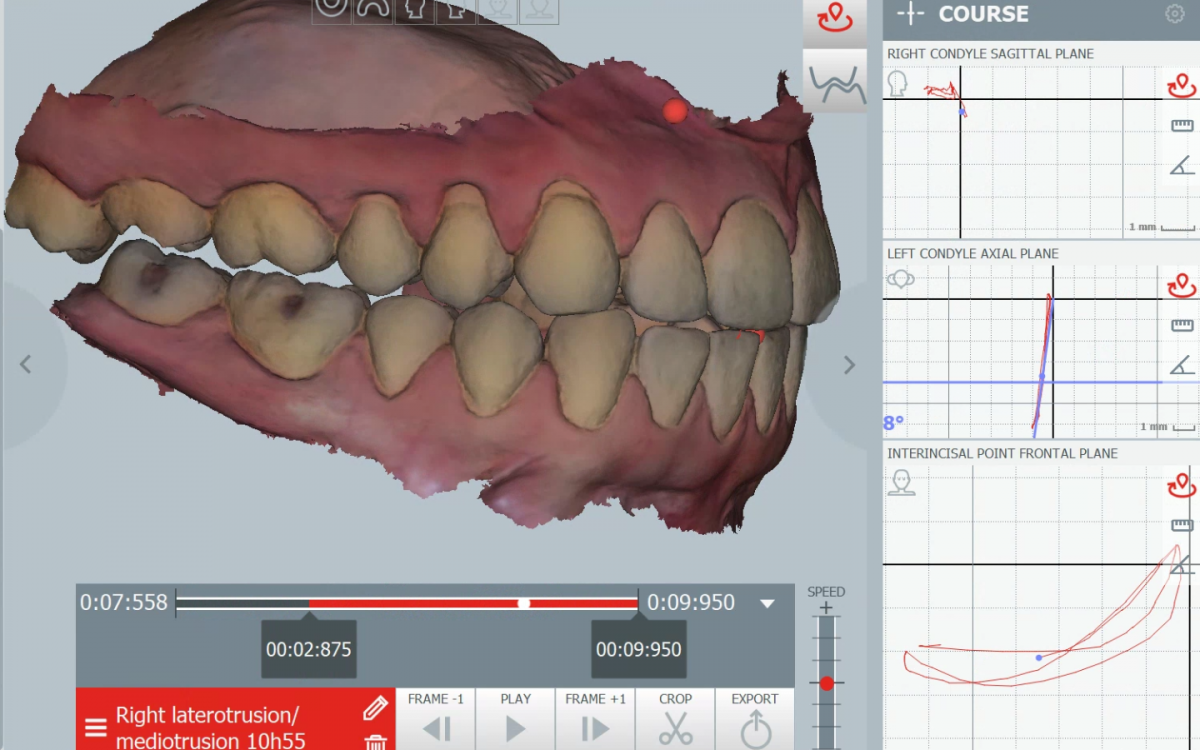

Jaw Tracking

Con la tecnología «Jaw Tracking» podemos identificar tu problema funcional y evaluar el resultado de nuestro tratamiento de manera objetiva.